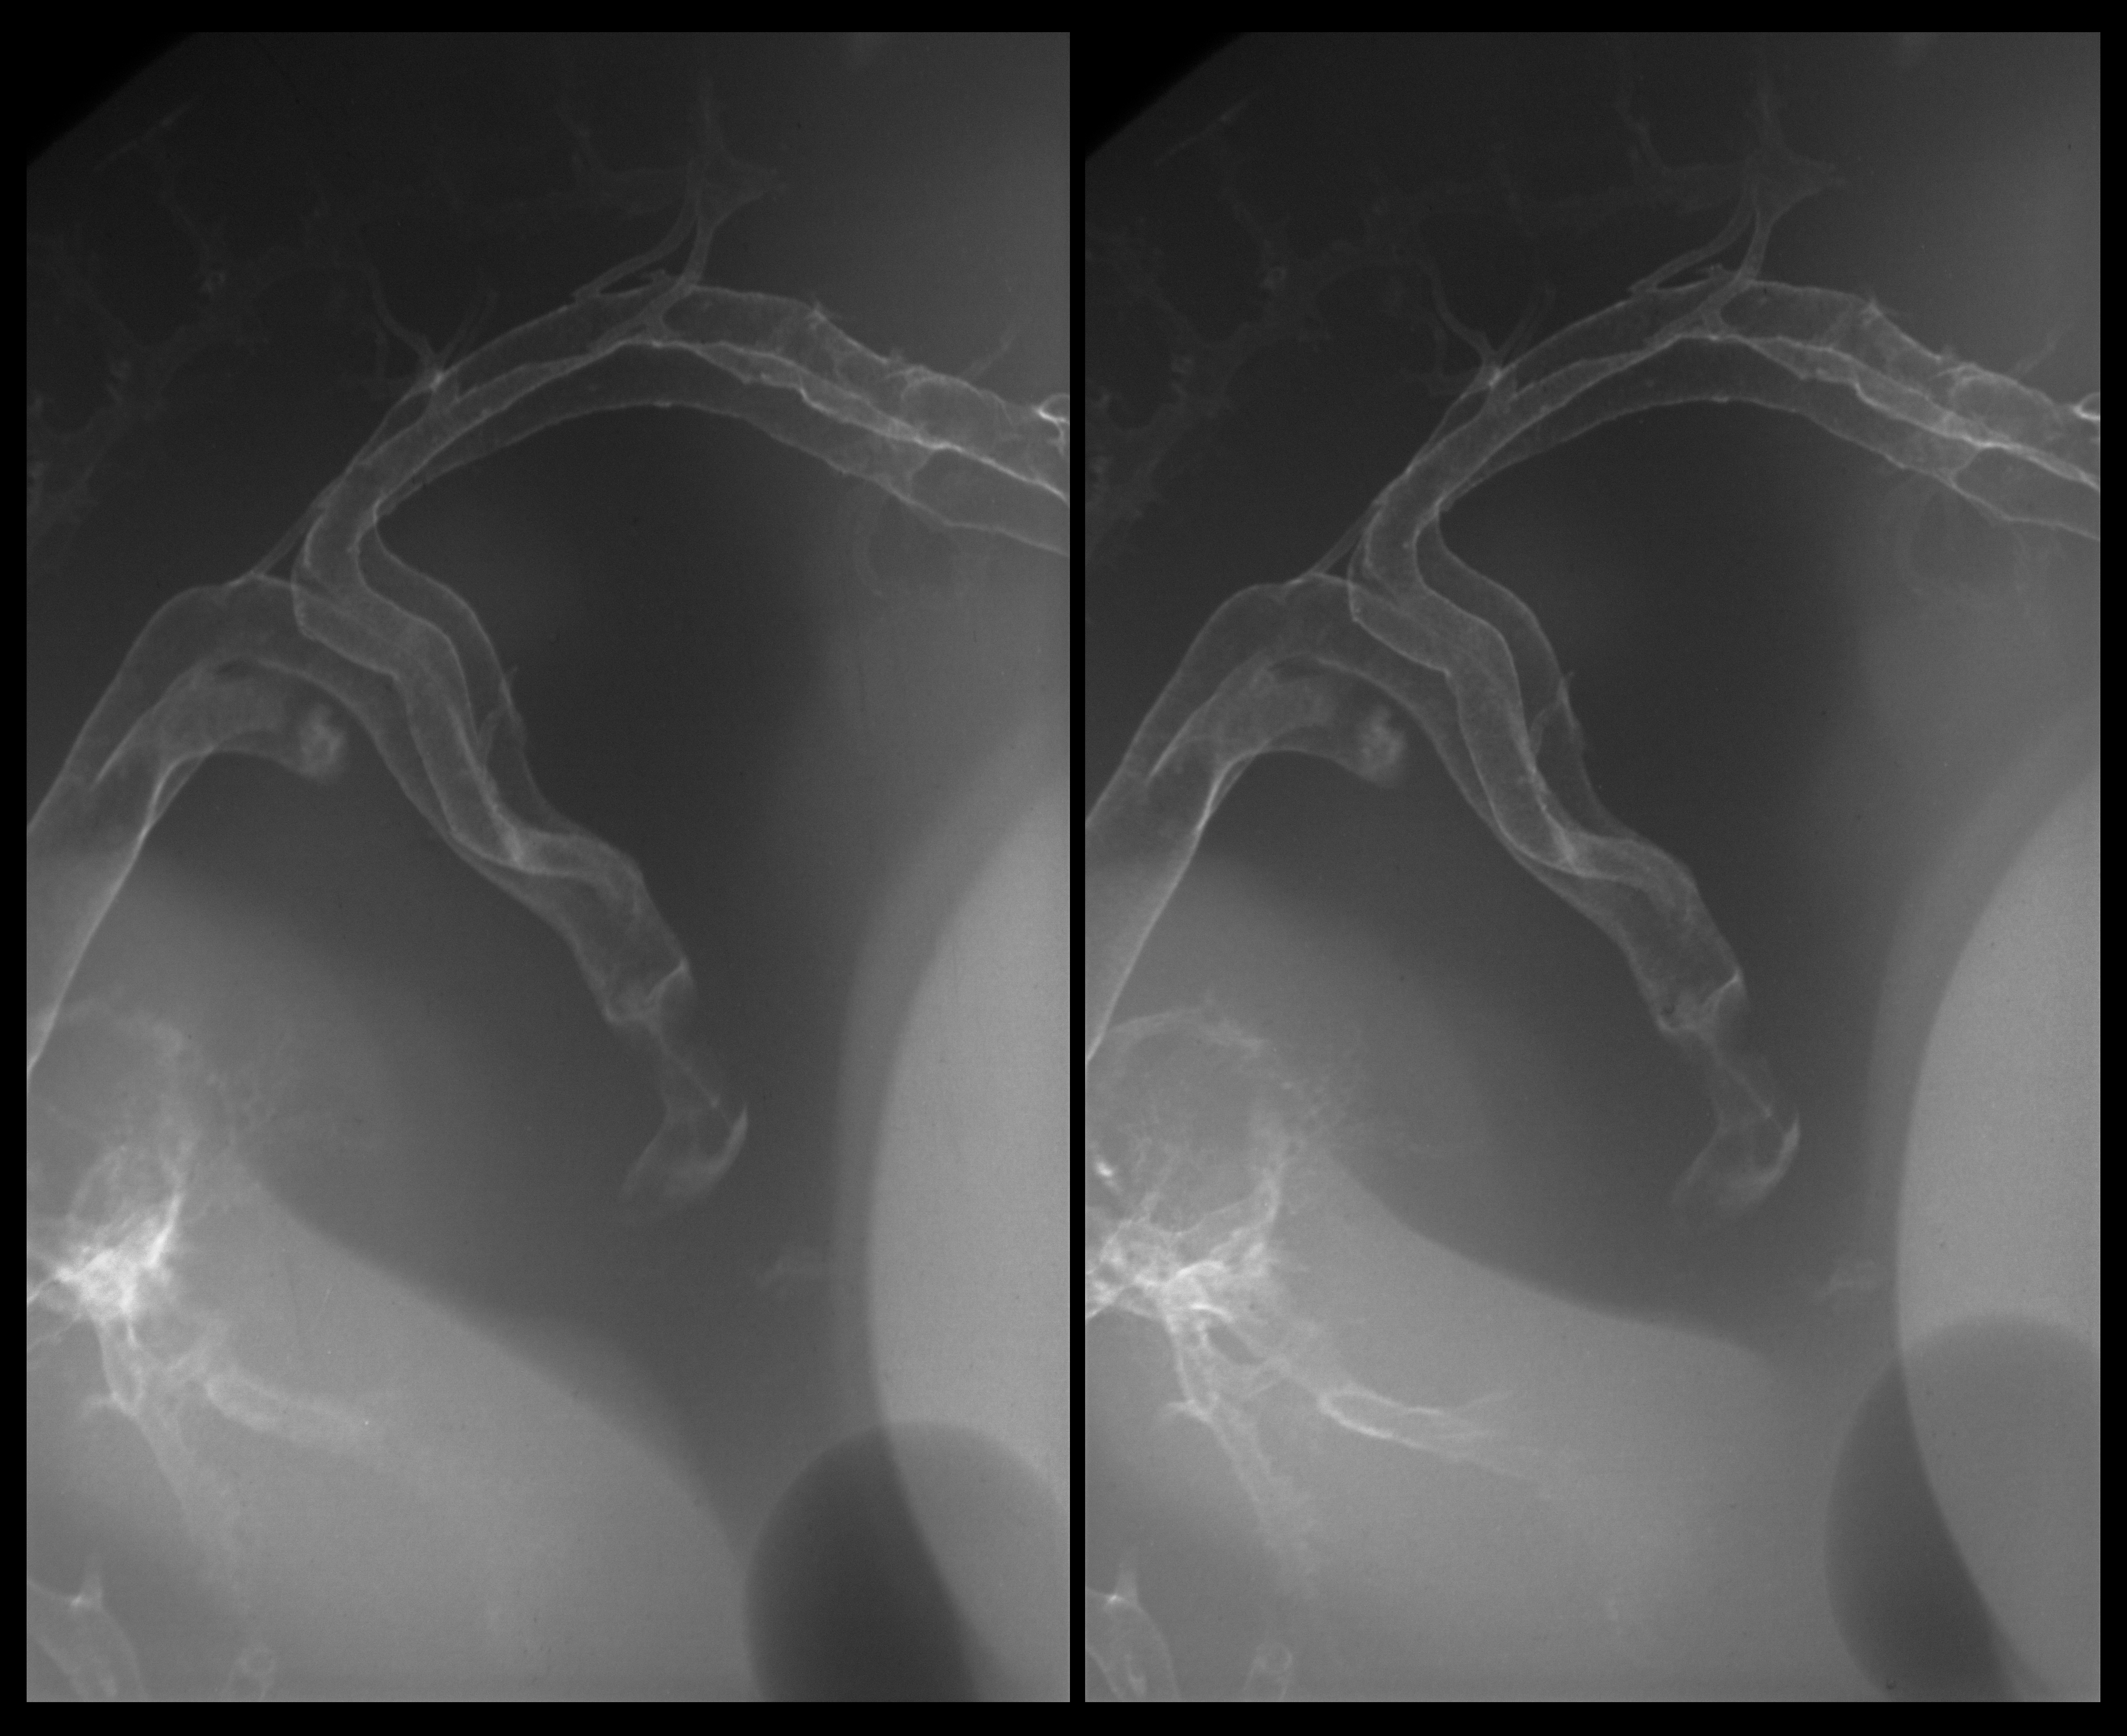

Chick Embryo Microangiography

Hamburger-Hamilton (HH) Stage 28 (approx. 5.5 - 6 days)

Drawing